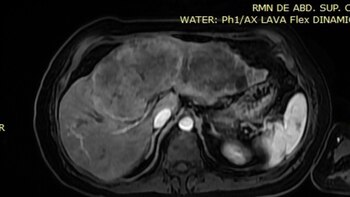

El procedimiento fue dirigido por Carlos Reyes Cruz, cirujano oncólogo integrante del equipo multidisciplinario del centro médico. La paciente consultó por presentar dolor torácico y abdominal intenso, junto con fatiga durante tareas cotidianas. Los exámenes de laboratorio y diagnóstico por imágenes detectaron a tiempo un carcinoma hepatocelular que comprometía estructuras vasculares y el sistema biliar.

Frente a este diagnóstico, los especialistas plantearon que la prioridad debía centrarse en salvar la mayor cantidad posible de parénquima sano, con el fin de asegurar la función vital del órgano. La cirugía, denominada triseccionectomía hepática, implicó la remoción de casi el 75 % del hígado.